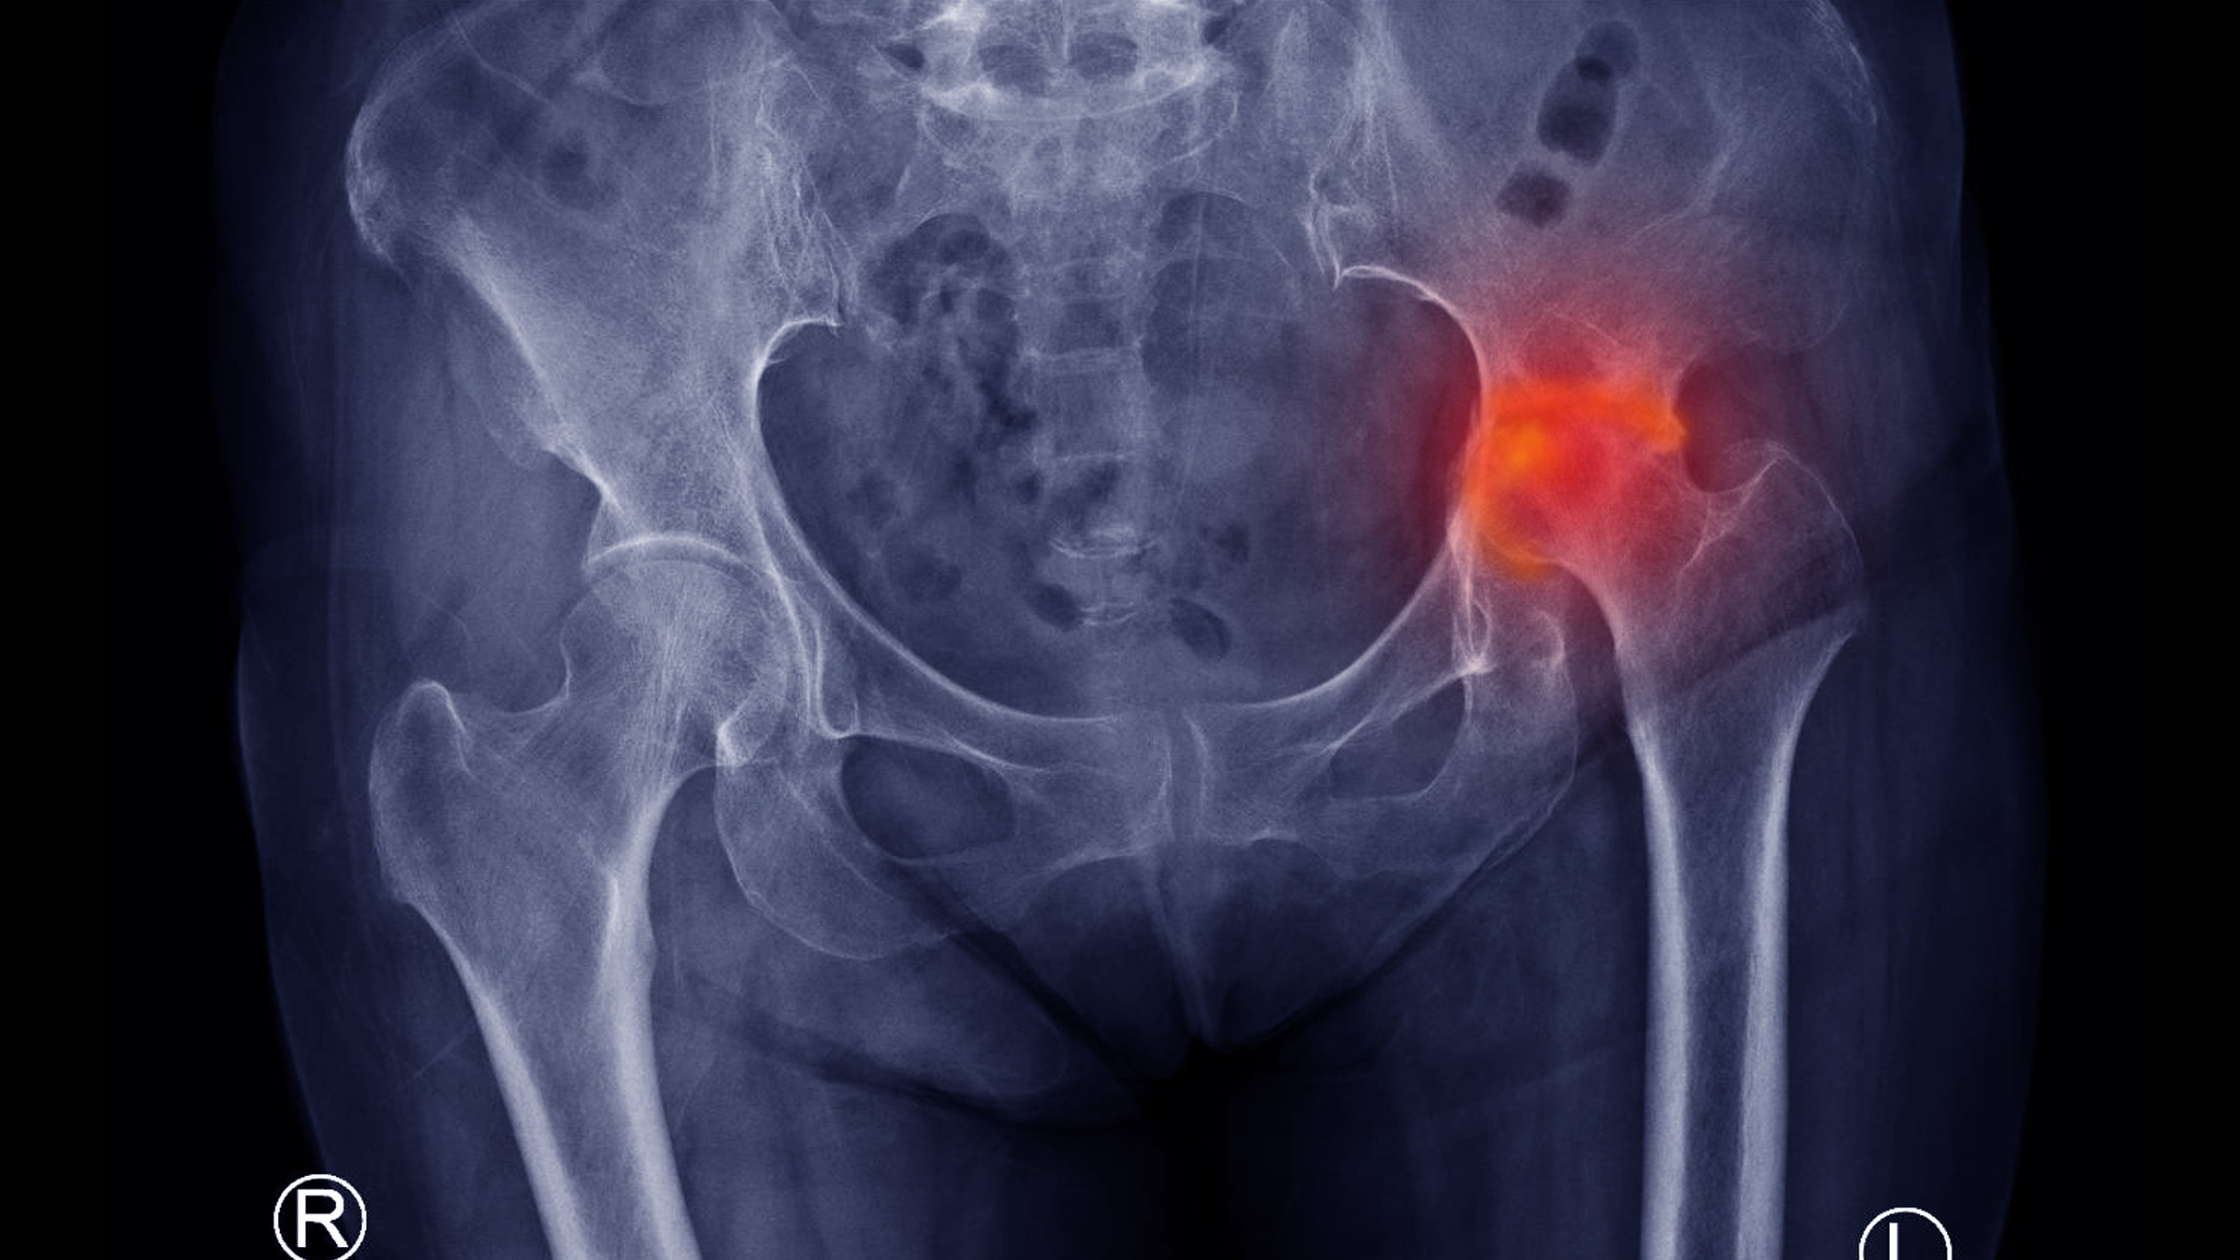

Today we are working at the frontier between what we know and what we need to know about osteonecrosis and Perthes’ Disease. Osteonecrosis means death of bone. This results from a wide variety of conditions, many poorly understood, which lead to major joint damage in children and young adults.